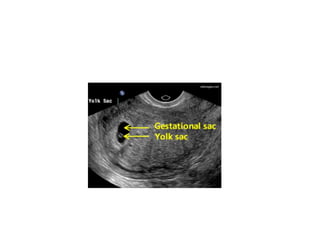

Pelvic ultrasound

• Most useful test in diagnostic evaluation of

women with suspected spontaneous abortion

• Foetal cardiac activity: most important (5.5-

6wks)

• Foetal heart rate

• Size & contour of G.sac

• Presence of yolk sac

• Best evaluated ,transvaginal approach(TVS)

• #16 The gestational sac (GS) is the first sign of early pregnancy on ultrasound and can be seen with endovaginal ultrasound at approximately 3-5 weeks gestation when the mean sac diameter (MSD) would approximately measure 2-3 mm in diameter.

• #17 The yolk sac is a membranous sac attached to an embryo, formed by cells of the hypoblast adjacent to the embryonic disk. The yolk sac is important in early embryonic blood supply, and much of it is incorporated into the primordial gut during the fourth week of development.